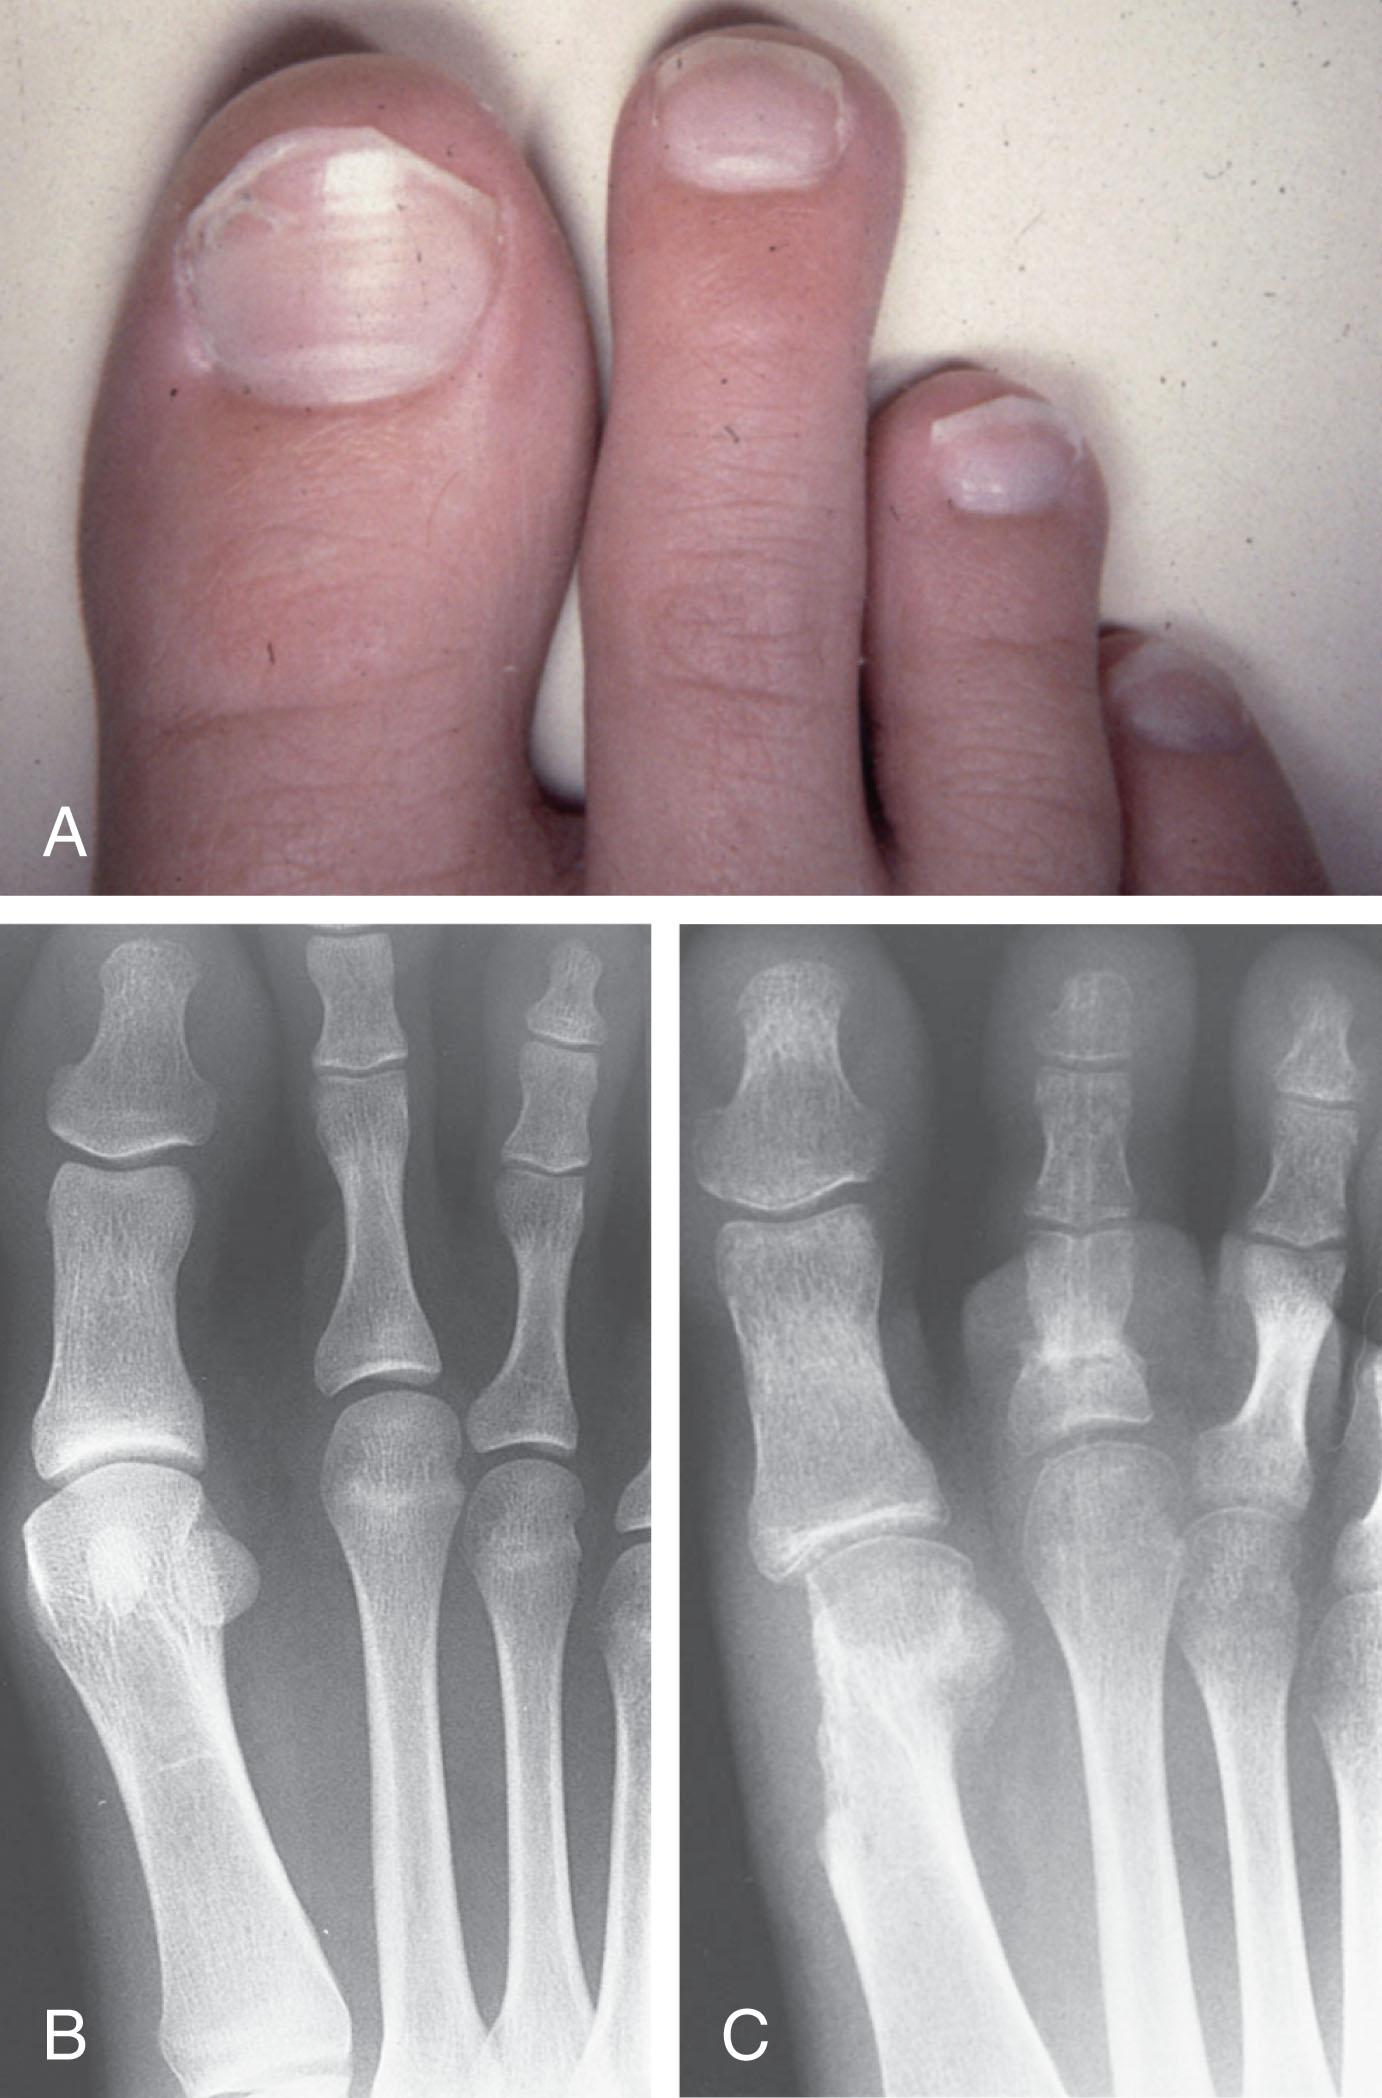

Mallet Toe

Other than its general relationship to pressure of the toe against the shoe, the specific cause of a mallet toe is unknown. Although most often idiopathic in nature, it can develop after a hammer toe repair or trauma or it can be associated with inflammatory arthritis. A mallet toe can also develop after a hammer toe repair, possibly because of scarring on contracture of the long flexor tendon. The high incidence of mallet toe in the female population has led to speculation that a constricting toe box is a causative factor. Female subjects constituted 84% of the patient population in one reported series. Brahms stated that a mallet toe is often limited to one toe, although Mann and Coughlin noted that the deformity can occur in more than one toe. Coughlin noted in 60 patients that 65% of patients had single toe involvement, while 18% of patients had three to five toes affected.

A mallet toe occurs with equal frequency in the second, third, and fourth toes, but most often the involved toe is longer than the adjacent toes ( Fig. 9-18 ). Because of pressure against the end of the shoe, the toe becomes plantar flexed at the DIP joint. Tightness of the flexor digitorum longus tendon in patients with a mallet toe deformity can be demonstrated, but whether this tightness is a primary cause or a secondary change is not known. In young children, a tight flexor tendon can result in a flexion deformity of the PIP and DIP joint. This pediatric deformity has been termed a curly toe and may also be associated with a delta-shaped phalanx.

The major symptoms leading to surgical repair in the adult population include discomfort because of pressure on the tip of the toe, with callus formation or dorsal pain over the DIP joint. Preoperative nail deformities occurred in 7% of mallet toes in Coughlin’s series, and 93% were noted to have dorsal pain or pain at the tip of the toe, with callus formation ( Figs. 9-19B and F and 9-20 C and D ).

Fig. 9-1, A , Mallet toe deformity with plantar flexion contracture of the distal interphalangeal (DIP) joint. B , Radiograph demonstrating a mallet toe deformity of the fourth toe.